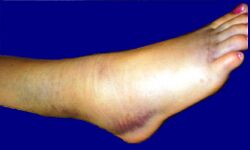

Отёк правого голеностопного сустава.

Повреждения (ушиб, вывих, перелом, растяжение связок), чаще всего возникают в результате прямого воздействия силы при ушибах и падении с высоты.

При растяжении связок голеностопного сустава быстро развивается отек вследствие кровоизлияния с внутренней или наружной стороны сустава, появляются резкие боли при подвертывании стопы внутрь. При пальпации под лодыжками ощущается резкая болезненность. Если одновременно с растяжением связок происходит перелом V плюсневой кости, то определяется резкая боль при пальпации её основания.